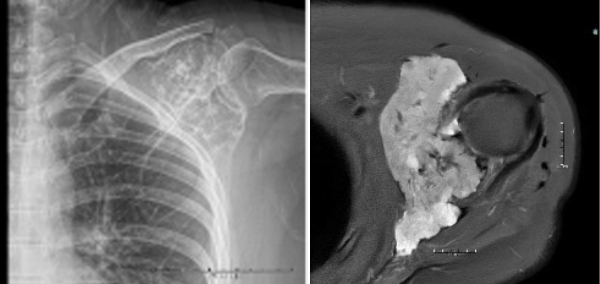

On physical examination, the patient’s left shoulder abduction was 45 degrees, limited by pain. Forward flexion was 90 degrees, limited by pain. Internal rotation on the left was to about the L5 spinal level, limited by pain. She also had pain with the drop arm test on left. Radiographs as well as advanced imaging revealed a well-demarcated lesion involving the scapula with no evidence of cortical destruction or soft tissue invasion (Figure 1).

Figure 1: Scapular radiograph and MRI showing evidence of an expansile lesion throughout the upper glenoid extending into the coracoid process.